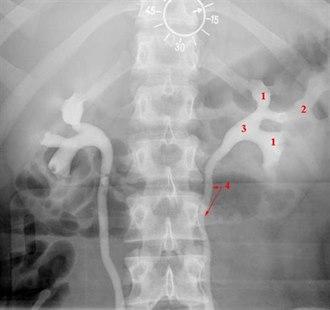

En normal røntgen urografi viser normal størrelse, form og posisjon av nyrer, urinledere og urinblære. Dersom nyrefunksjonen er normal, skal kontrastoppladning i nyrene synes på røntgen 2-5 min etter kontrastinjeksjonen. Etter 5-7 min skal nyrebekkenet være synlig. Senere bilder viser urinlederne og urinblæren som uttrykk for at kontrastvæsken passerer ned i de nedre urinveier. Etter urintømning skal det ikke være urin igjen i blæren.

Oversiktsbildet kan vise forkalkninger, f.eks. nyrestein. Etter kontrastinnsprøytingen gransker røntgenlegen om nyrene er i normal posisjon, om nyrekonturene er normale, om nyrene er normalt store, om nyren og nyrebekkenet ser normale ut, om urinlederne har normal størrelse eller om det er tegn til tilstopping og tilslutt om urinblæren ser normal ut.

De vanligste unormale funn er endringer i størrelse, form og posisjon til nyrene, nyrebekkenet og urinlederne. Tilstopping i urinveiene skyldes i de aller fleste tilfeller nyrestein, sjeldnere en svulst som har vokst inn i urinlederen. Funn av nyrecyster (cyste er et væskefylt hulrom) er et hyppig funn og er som regel uten betydning, men kan være vanskelig å skille fra svulster på urografi. Svulster kan gi en utbukning på nyrekonturen, eventuelt en forskyvning av strukturer inne i nyren, eventuelt økt nyrestørrelse - særlig hvis oppfylningen ligger ved den ene nyrepolen. Et slikt funn vil bli utredet videre med ultralyd eller CT. Forøvrig er det mulig å påvise en lang rekke mer eller mindre sjeldne tilstander ved urografi, men det vil føre for langt å beskrive disse her.